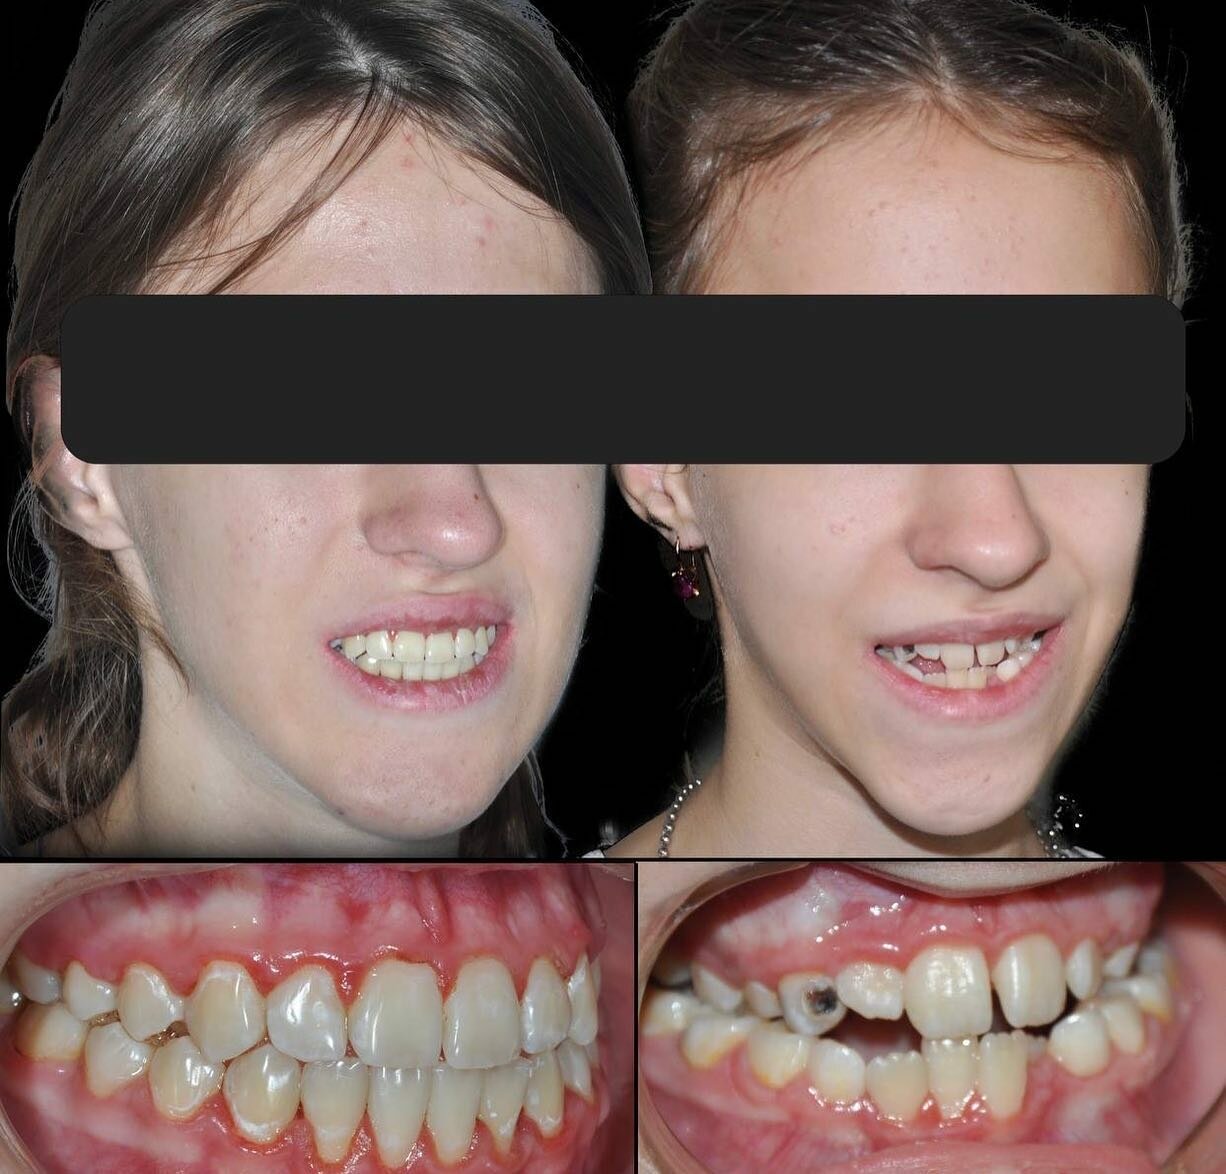

- ортодонтия

- брекеты

- Положительные впечатления от консультации и установки брекетов.

- Отрицательные последствия лечения (выпадение зубов, испорченный прикус).

- Халатность ортодонта (непунктуальность, некачественное лечение).

- Недовольство качеством ортодонтического лечения (потраченные время и деньги без результата)

Ортодонт Эльдар халтурщик не пунктуальный 6 лет и 75 тр на воздух. Не отдавайте всю сумму на перёд а к нему вообще не ходите. Что по мне в шею его гнать надо. И таких как он.

Записывался на консультацию и дальнейшую установку брекетов для исправления прикуса. Впечатления на данный момент только положительные. Работа аккуратная, отношение вежливое, дополнительных услуг не навязывали.